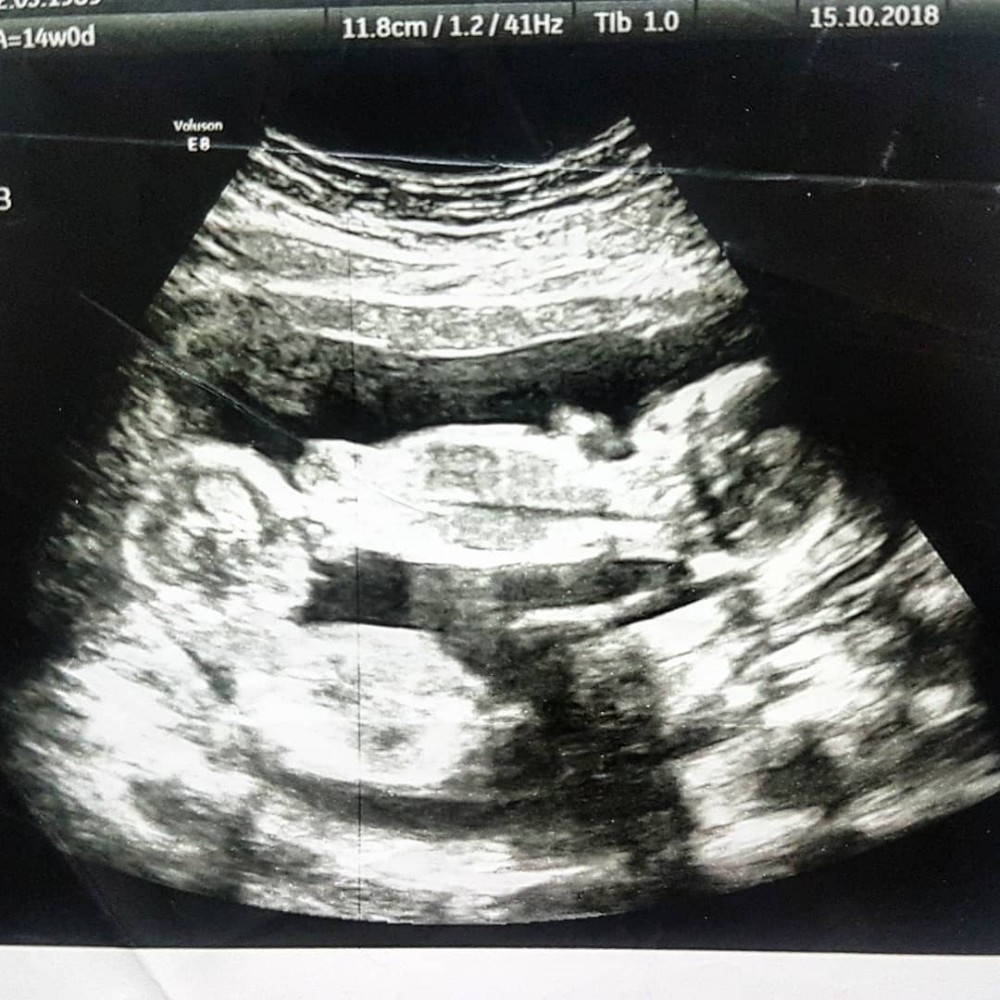

澳洲有媽媽喺懷孕14周時,發現自己懷上同卵雙胞胎,但雙胞胎不幸係1%罕見單絨毛膜單羊膜類,導致喺7個月時需要剖腹生產。

由於2個胎共用一個胎盤同羊膜,2個BB之間幾乎無阻隔,容易會發生臍帶互纏導致缺氧,存活至6個月嘅機率只有五成。